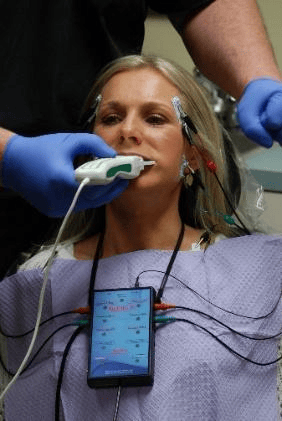

Computer analysis of the bite using high tech interocclusal sensors (T-Scan 10 Novus High Definition sensors, Tekscan Inc., Norwood. MA USA, www.tekscan.com/dental) and simultaneous surface electromyography (BioEMG III, Bioresearch Assoc., Milwaukee, WI. USA, BioResearch Associates) (Figures 1a and b), have isolated the main culprit of many chronic conditions as being the frictional time-durations that opposing posterior teeth push each other in and out of their sockets and bend each other on their axes from prolonged bite surface friction that occurs when teeth are functioning.3,6,12,13

Figure 1a– The T-Scan 10/BioEMG III can simultaneously record a patients bite function and the muscular response to that bite function.

Figure 1b – The T-Scan High Definition Bite Force Sensor in the Novus recording handle that together capture changing dynamic bite forces in differing chewing movements.